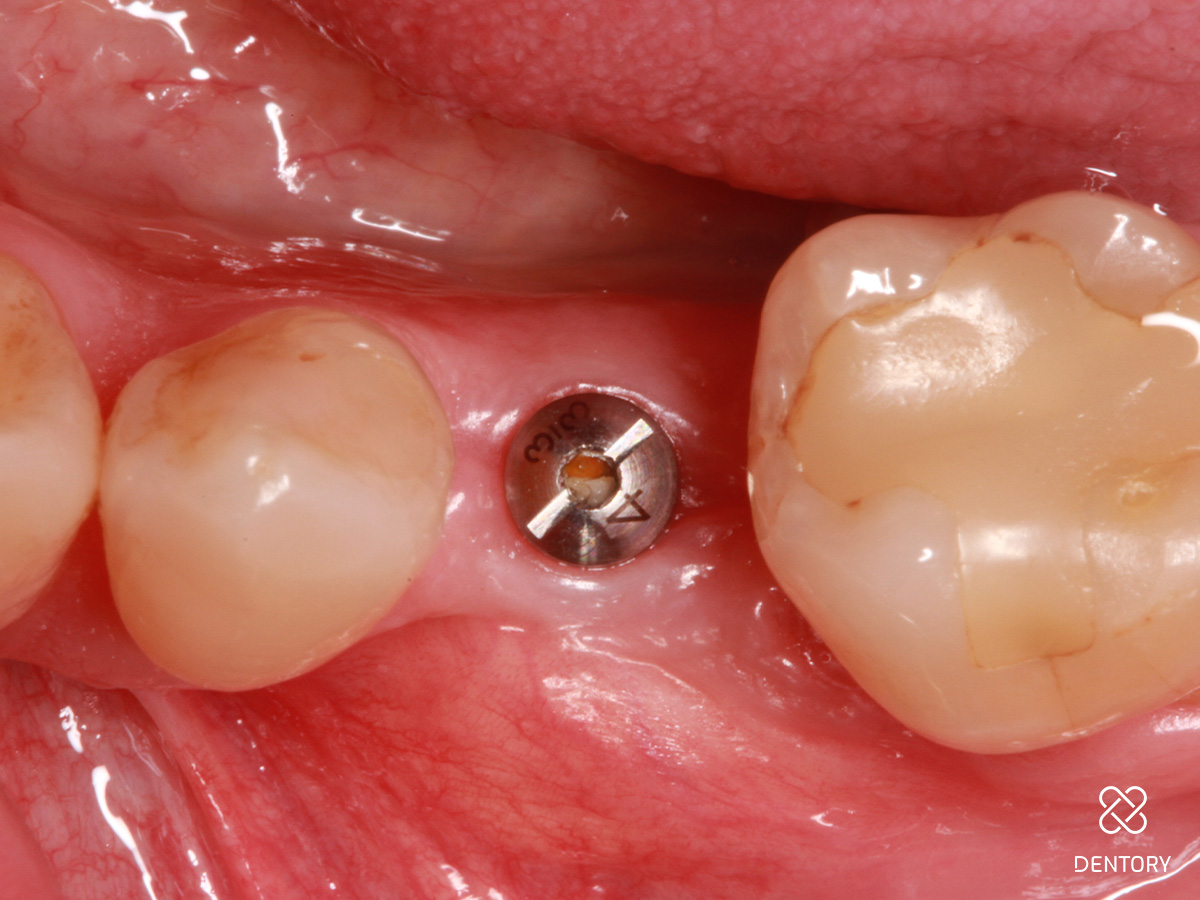

Abbildung 1

Ausgangssituation: Einzelzahnlücke regio 35.